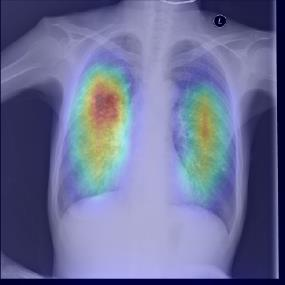

Chest X-ray (CXR) is the most typical diagnostic X-ray examination for screening various thoracic diseases. Automatically localizing lesions from CXR is promising for alleviating radiologists' reading burden. However, CXR datasets are often with massive image-level annotations and scarce lesion-level annotations, and more often, without annotations. Thus far, unifying different supervision granularities to develop thoracic disease detection algorithms has not been comprehensively addressed. In this paper, we present OXnet, the first deep omni-supervised thoracic disease detection network to our best knowledge that uses as much available supervision as possible for CXR diagnosis. We first introduce supervised learning via a one-stage detection model. Then, we inject a global classification head to the detection model and propose dual attention alignment to guide the global gradient to the local detection branch, which enables learning lesion detection from image-level annotations. We also impose intra-class compactness and inter-class separability with global prototype alignment to further enhance the global information learning. Moreover, we leverage a soft focal loss to distill the soft pseudo-labels of unlabeled data generated by a teacher model. Extensive experiments on a large-scale chest X-ray dataset show the proposed OXnet outperforms competitive methods with significant margins. Further, we investigate omni-supervision under various annotation granularities and corroborate OXnet is a promising choice to mitigate the plight of annotation shortage for medical image diagnosis.